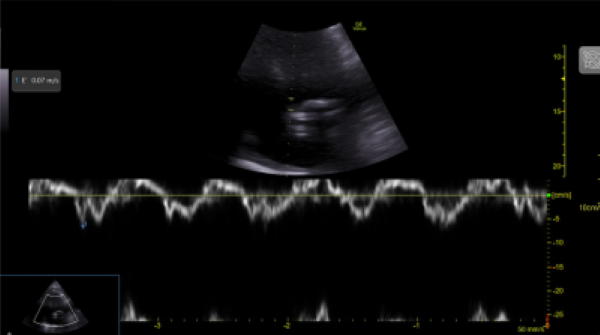

Image 3. Tissue Doppler Imaging shows mitral annular e’ velocity 7 cm/s. Mitral inflow shows pseudonormal LV filling pattern consistent with elevated LV filling pressures and classified as grade 2 diastolic dysfunction.

To measure diastolic dysfunction, start by obtaining an apical four chamber, place pulse-wave doppler over the tips of the mitral valve leaflets, and transmitral velocity times can be measured (Image 2). Peak E wave velocity correlates with early diastolic filling rate, mitral annular e’ velocity reflects LV relaxation rate (Image 3), and both values are used to calculate E/e’ which correlates with left ventricular filling pressures.

This patient has risk factors for diastolic dysfunction, such as left systolic dysfunction and regional wall abnormalities. His E/A is above the cutoff of 0.8 (E/A 1.72), which is characteristic of normal or pseudonormal inflow pattern. The E/e’ is low, classified as having grade 2 diastolic dysfunction, and implicating that the mean LA pressure is elevated.